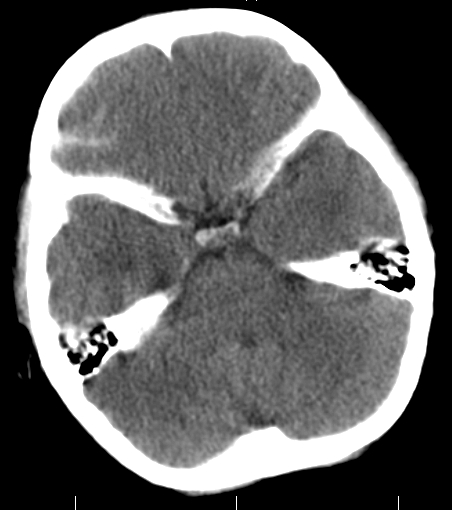

女,3岁,头部外伤一小时。半卵圆中心低密度是什么意思,病灶?侧脑室?请指教。

从层面看不是侧脑室,考虑低密度变,建议mri。

不是侧脑室,考虑正常脑白质。为慎重,建议mr!